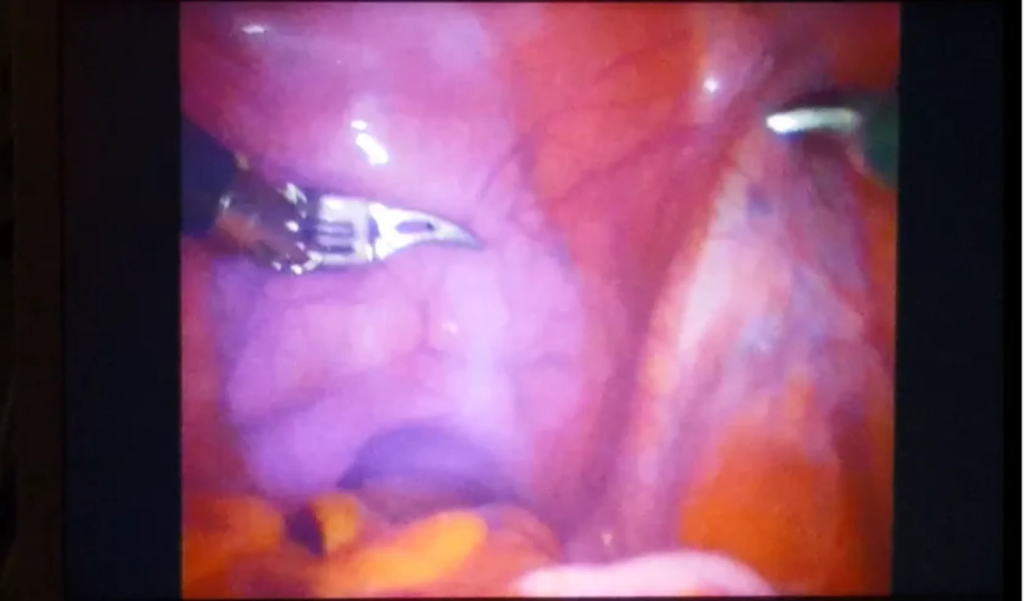

Surgeons begin a radical prostatectomy in the ProMOTE study, with prostate and lymph node tissue made visible by the purple dye.

In a preliminary study involving 23 men undergoing prostatectomies, the dye successfully attached to proteins on cancer cells, highlighting them for the surgical team with the help of a specially designed imaging system. Cutting out cancerous cells is crucial to curing the disease in early stages, but it can be extremely difficult to catch those that have spread outside the main tumors to lymph nodes and other areas of the pelvis.

The dye, which is linked to a molecule that targets Prostate-Specific Membrane Antigens, or PSMA, was developed at the University of Oxford in collaboration with a Southern California-based biotech company. A larger trial is currently underway in the U.K., and researchers are hopeful the dye could one day be used for other types of cancers as well.

Because the dye-molecule combination allows for more specificity in removing cancerous cells, it also minimizes damage to healthy pelvic tissue.